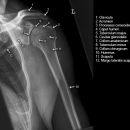

Schulter seitlich (Y-View)

Bei Luxation zusätzlich zur glenoidtangentialen Aufnahme problemlos durchführbar! Axiale Aufnahme schmerzbedingt meist nicht möglich.

Beurteilungskriterien

- Skapula bildet sich als Y ab

- Humeruskopf projiziert sich in das Glenoid? Luxation? Luxationsrichtung?

- Weite des subacromialen Raumes exakt nur in der 10 – 15° nach kaudal angulierten Aufnahme bestimmbar („Morrison, Outlet View“)! Normalerweise 1 - 1,5 cm, < 6 mm -> wohl pathologisch, Impingment wahrscheinlich

- Normvarianten: Os glenoidale (akzessorischer Ossikel kaudal des Glenoids), persistierende Akromion- oder Korakoidapophyse, entwicklungsbedingte Pfannenranddefekte

- Schulterluxationen:

- Anteriore Luxation (2) 95%= anteriore infraglenoidale Luxation, Kopf liegt vor Glenoid

- Posteriore Luxation (2) 3%: wird häufig übersehen! Kopf liegt hinter Glenoid, Hochstand des Humeruskopfes, fixierte Innenrotation des Humeruskopfes => atypische Projektion des Humeruskopfes: “ drumstick or bulb appearance“ (Birnenform), Muldenzeichen („trough line“), „rim sign“ in der ap bzw. glenoidtagentialen Aufnahme.

Zweite Ebene, z.B. transskapuläre Aufnahme zeigt die Richtung der Luxation. Cave. rein klinische Diagnose!

- Begleitverletzungen? (-> heute umfassend mit CT/MRT zu beurteilen)

- Tuberculum majus (15%)

- Pfannenrand

- Hill- Sachs Läsion = Dorsokraniale Humeruskopf-Impressionsfraktur (50%) (Aufnahme der 1. Wahl: Stryker oder CT)

- umgekehrte Hill-Sachs Läsion = anteromediale Impression nach hinterer Luxation

- Bankart-Läsion: Abriss des vorderen Labrum-Kapsel-Komplexes bzw. Abrissfraktur des vorderen unteren Glenoidrandes (-> CT-Athrographie, Arthro-MRT)